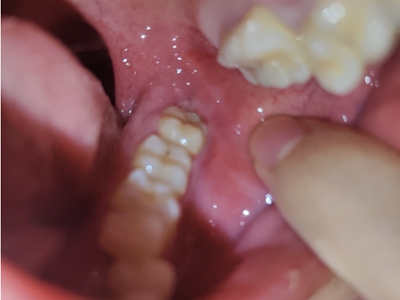

智齿冠周炎右下方智齿牙龈处有小疙瘩图

智齿冠周炎患者口腔右下方智齿的牙龈处有一小疙瘩,小疙瘩表面红肿,边缘微微发白,可见少量的牙齿萌出,周围黏膜有明显的充血、发红样。